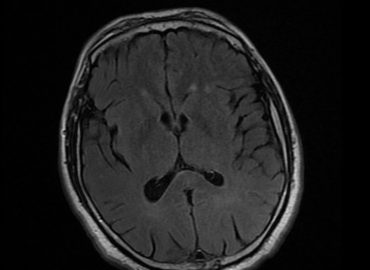

Paciente masculino de 47 años con antecedente de trasplante renal. Consulta a la guardia refiriendo cefalea de 48 hs de […]